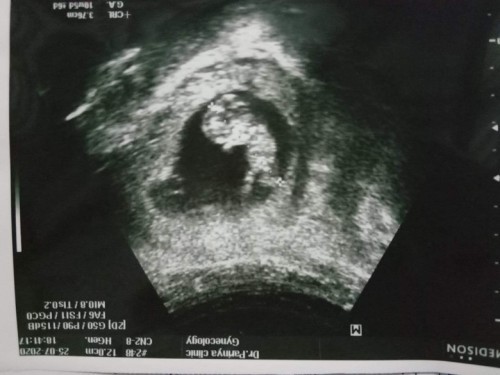

ซาวครั้งแรก

ขอดูใบซาวหน่อยค่ะ แม่ๆบ้านไหน กำหนดคลอดเดือน กุมภา 64 บ้างค่ะ บ้านนี้กำหนด 14กุมภา64